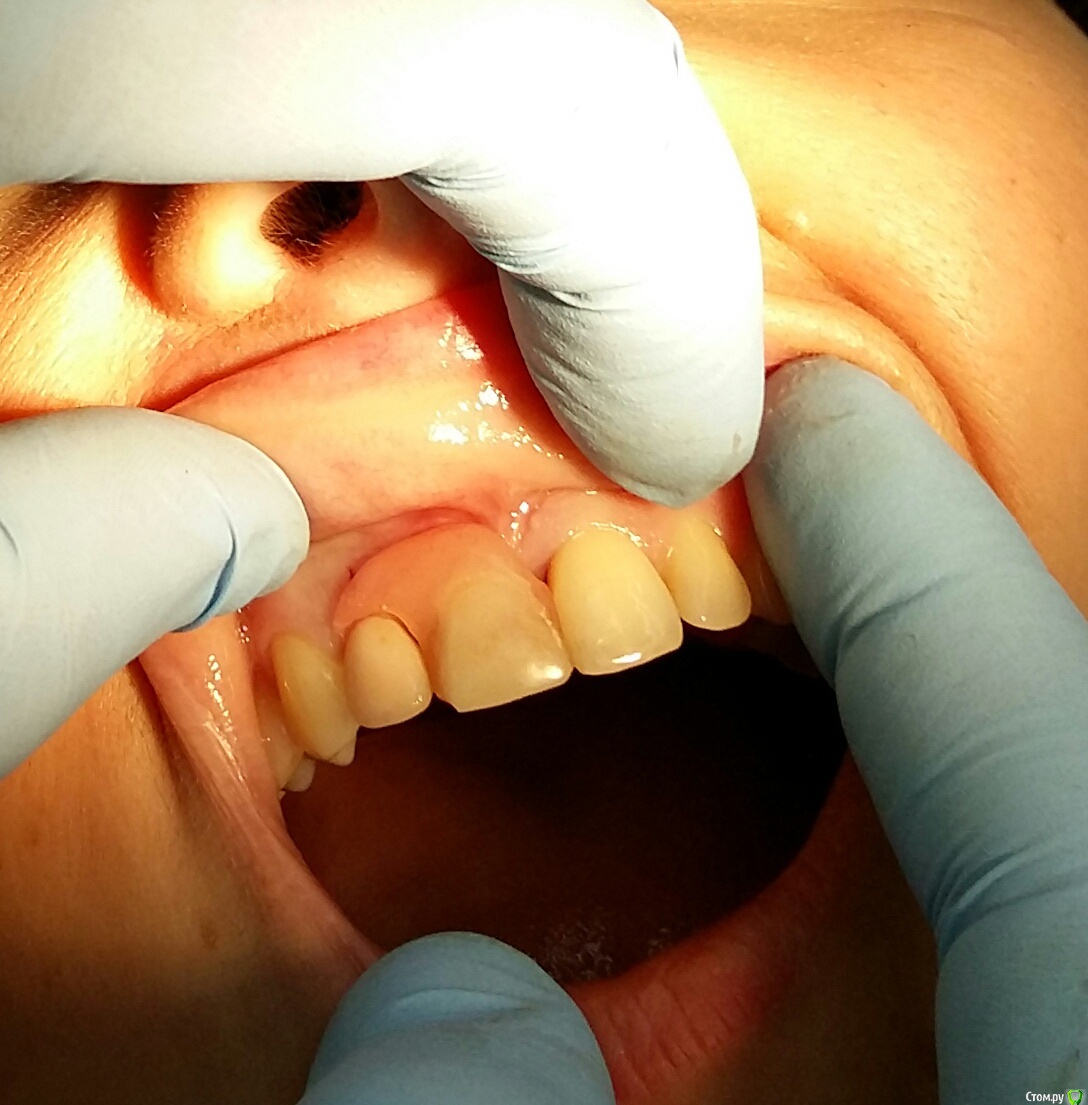

Kostoprav Опубликовано 18 марта, 2015 Поделиться Опубликовано 18 марта, 2015 сделал сокет презервейшен , в лунке графт без гиперобъема . По началу все было ок, но после снятия швов лоскут начал переть)Что делать и почему он разбух-ваше мнение коллеги? P.S. хотелось бы сделать временную конструкцию Ссылка на комментарий

DentArt Опубликовано 18 марта, 2015 Поделиться Опубликовано 18 марта, 2015 сделал сокет презервейшен , в лунке графт без гиперобъема . По началу все было ок, но после снятия швов лоскут начал переть)Что делать и почему он разбух-ваше мнение коллеги? P.S. хотелось бы сделать временную конструкциюПо фото,,, жизнеспособность слизистой в месте манипуляции под огромным вопросом? Что делать? Наблюдать в динамике! Ни о каких временных конструкциях речь даже идти не может,,, Ссылка на комментарий